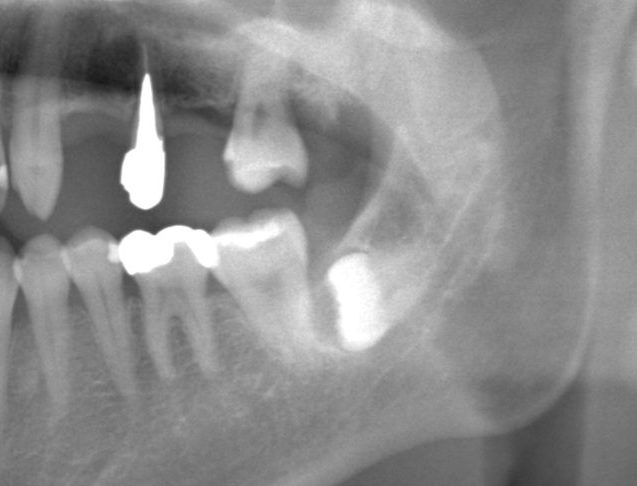

パノラマレントゲンによる埋伏歯(親知らず)の診断画像。水平埋伏や骨内埋伏など、周囲の歯や骨との位置関係を確認できます。